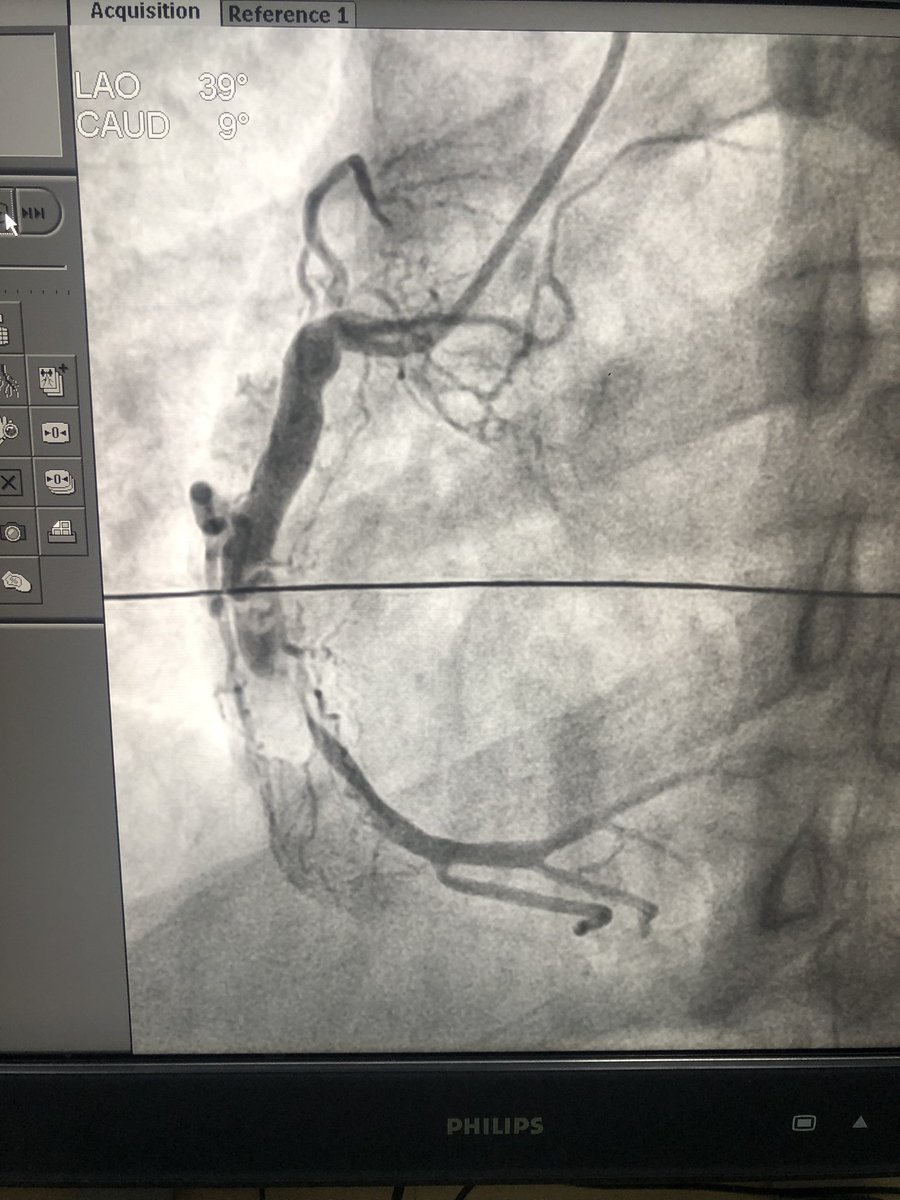

Can u beleive the pt is just 28! Ectatic bag of an RCA with thrombotic ugly lesion